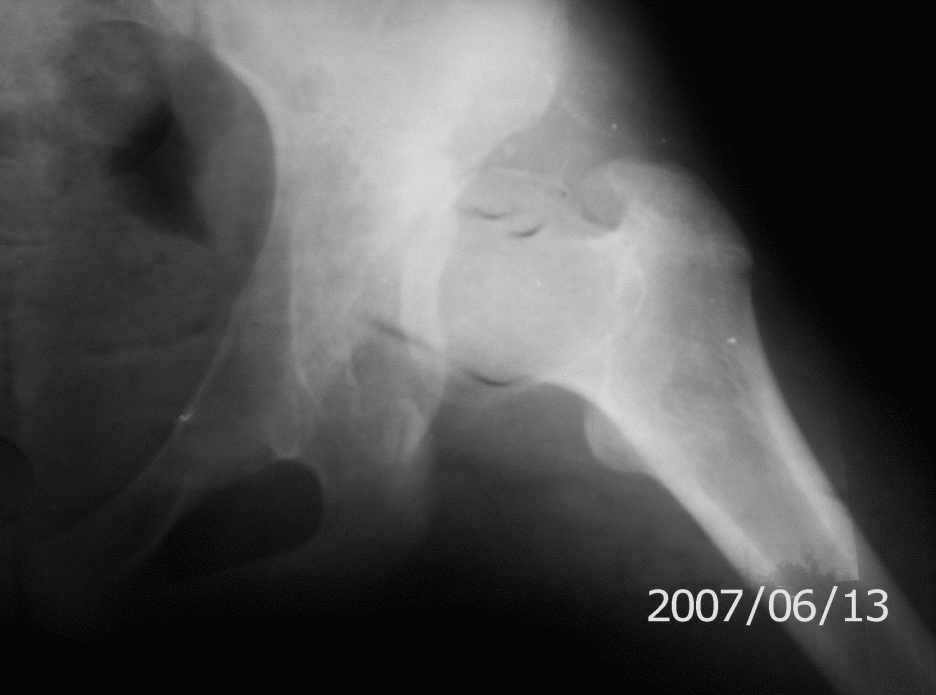

On x-rays coxa magna, shallow true + pseudoacetabulum.Options: salvage

( Shelf /Chiari) or triple osteotomy.Trudno otvetit bez at least basic x-rays.

Ацетабулюм крайне недоразвит. Есть высокий подвывих, можно даже сказать вывих с формированием ложного ацетабулюм. Для головки нет покрытия совсем и расположена она высоко.

На мой взгляд - SHORTENING OSTEOTOMY , VARUS если надо (на основании снимка во внутренней ротации), репозиция головки, CHIARI OSTEOTOMY или SHELF OPERATON Спасибо за интересный случай.